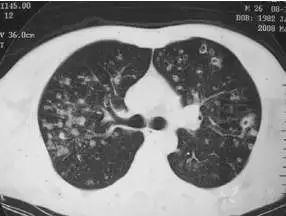

隐球菌感染导致的颅内胶状假性囊肿 病灶